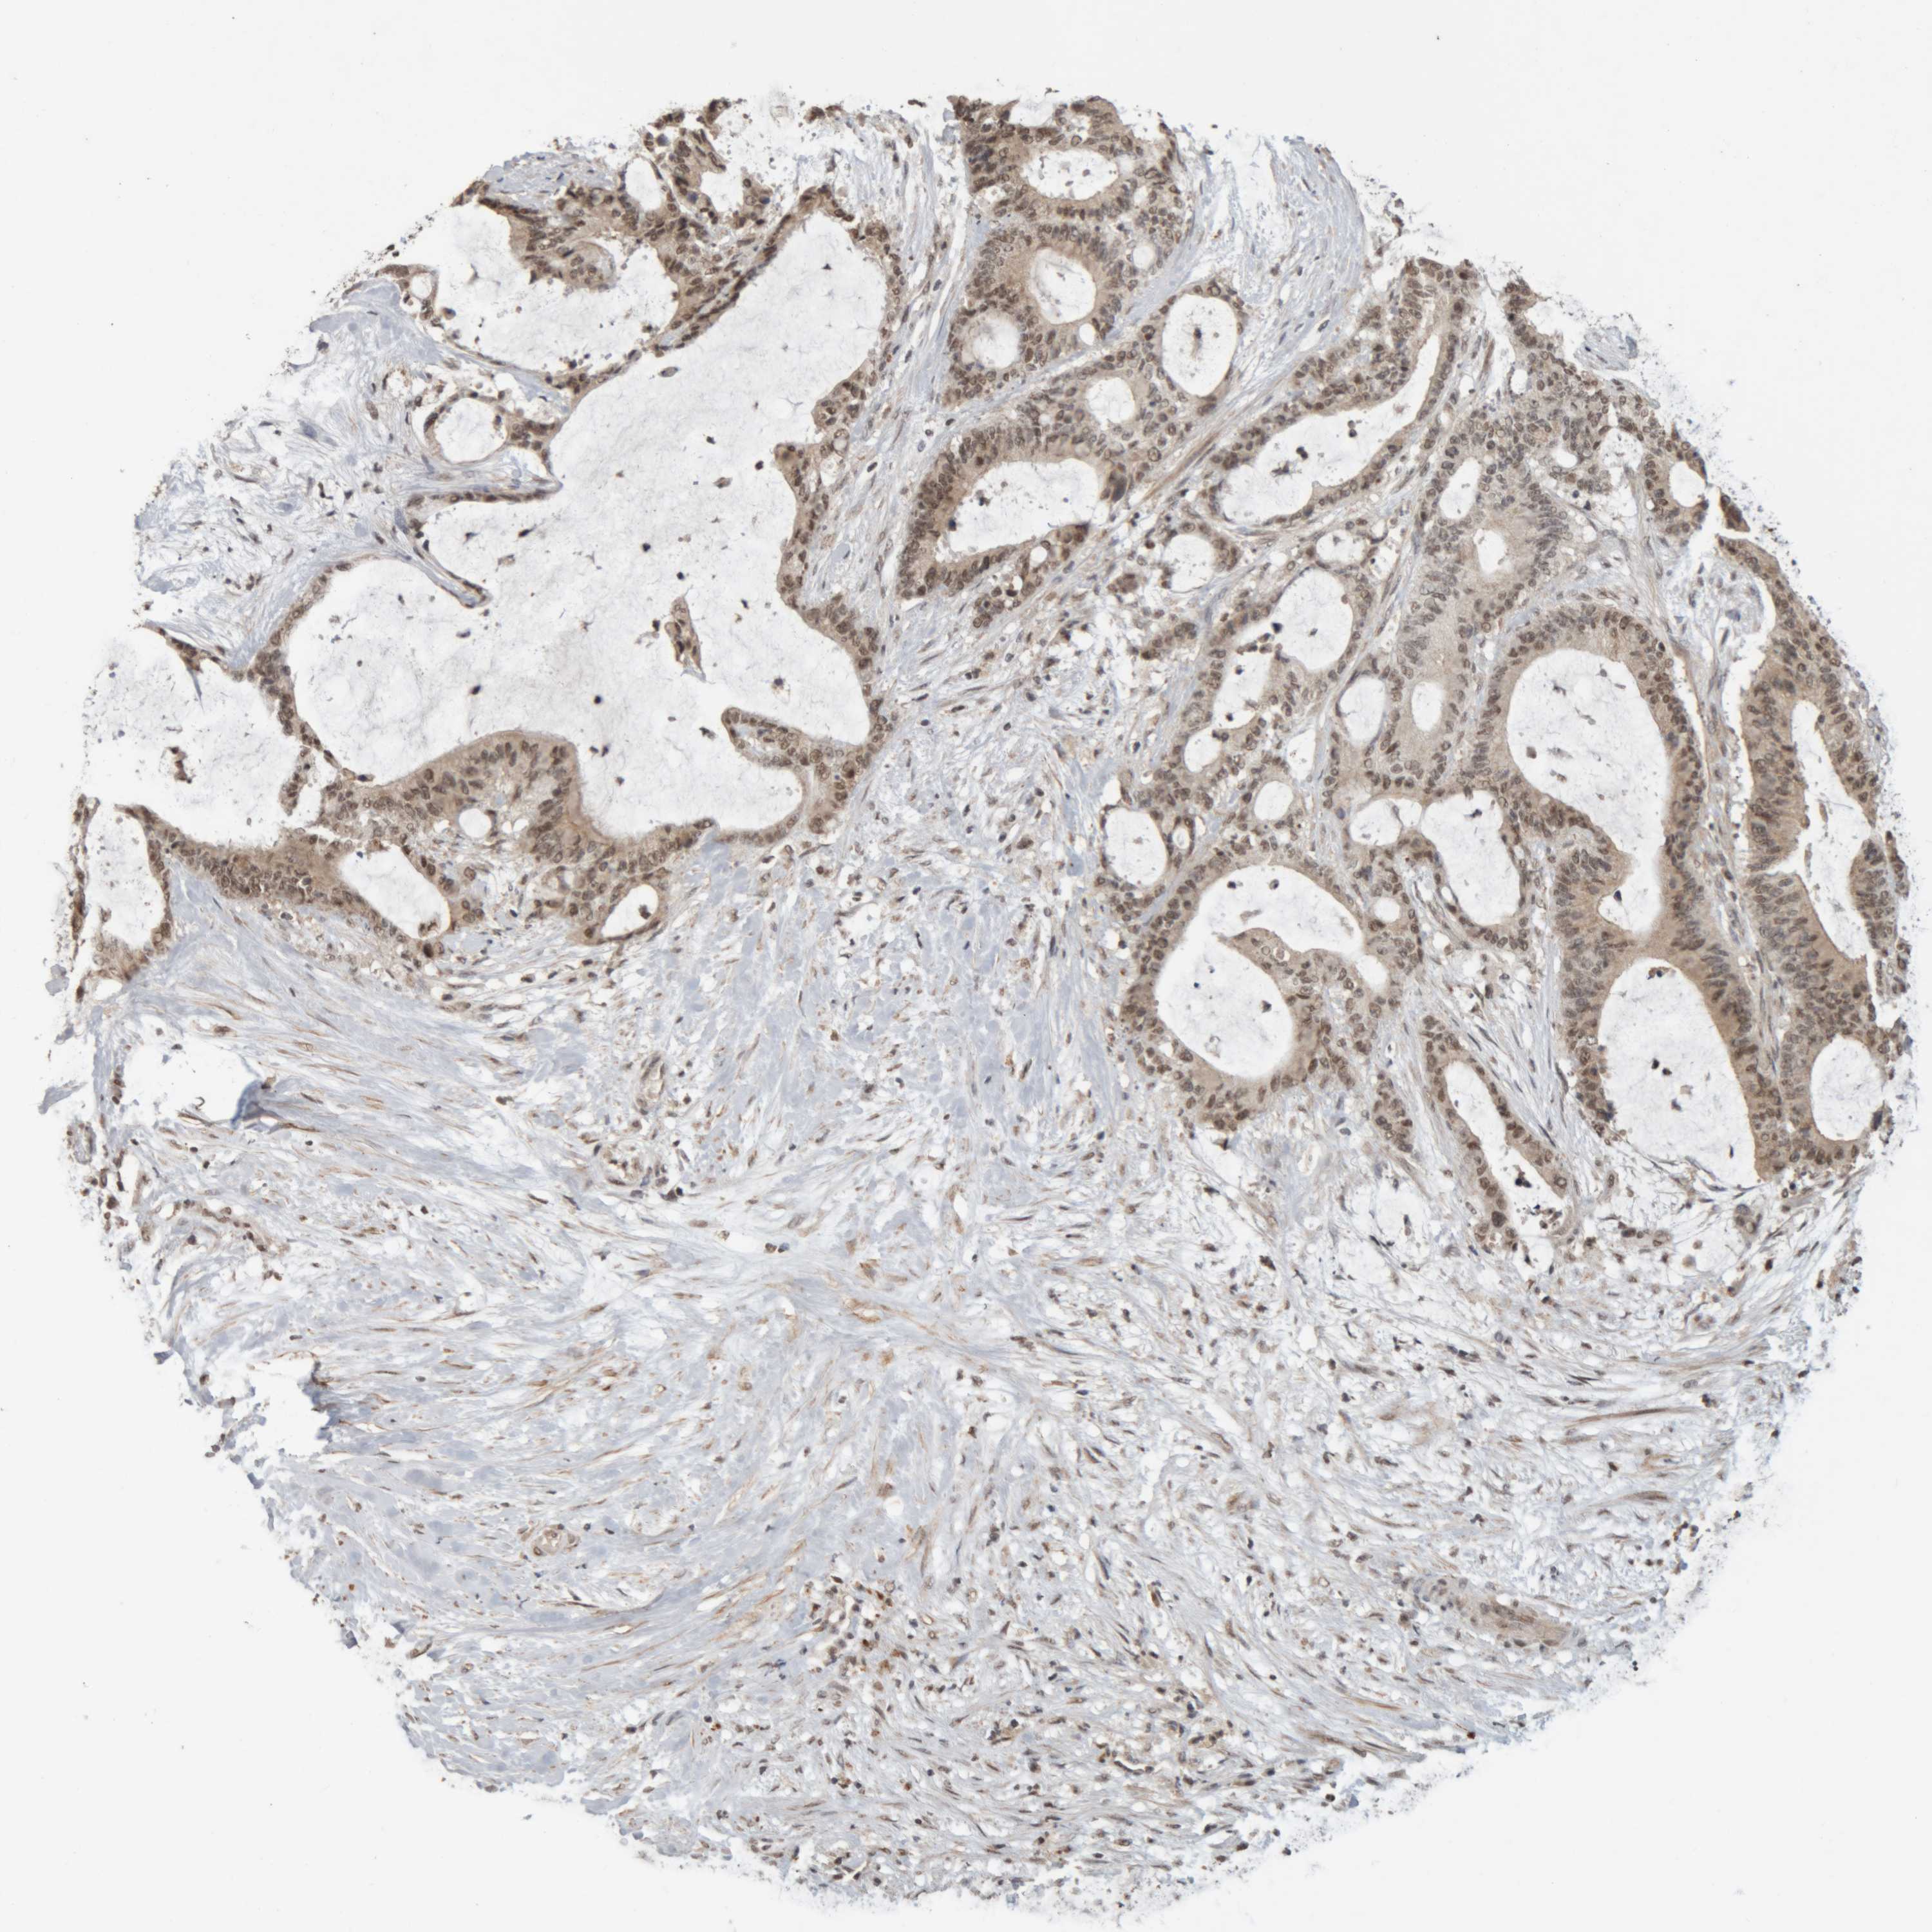

LIVER CANCER - Protein expressioni

A mouse-over function shows sample information and annotation data. Click on an image to view it in a full screen mode. Samples can be filtered based on level of antibody staining by selecting one or several of the following categories: high, medium, low and not detected. The assay and annotation is described here.

Note that samples used for immunohistochemistry by the Human Protein Atlas do not correspond to samples in the TCGA dataset.

Antibody stainingi

Antibody staining in the annotated cell types in the current human tissue is reported as not detected, low, medium, or high, based on conventional immunohistochemistry profiling in selected tissues. This score is based on the combination of the staining intensity and fraction of stained cells.

Each image is clickable and will lead to virtual microscopy that enables deeper exploration of all samples and also displays staining intensity scores, fraction scores and subcellular localization as well as patient and tissue information for each sample.

Antibody HPA005558

Antibody CAB025337

Staining

High

Medium

Low

Not detected

Intensity

Strong

Moderate

Weak

Negative

Quantity

>75%

75%-25%

<25%

None

Location

Nuclear

Cytoplasmic/membranous

Cytoplasmic/membranous,nuclear

Cholangiocarcinoma

Carcinoma, Hepatocellular, NOS